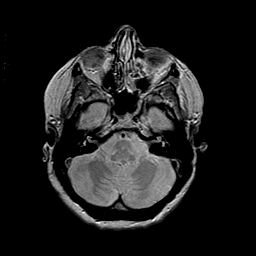

MR Study #2 -- Slice #14